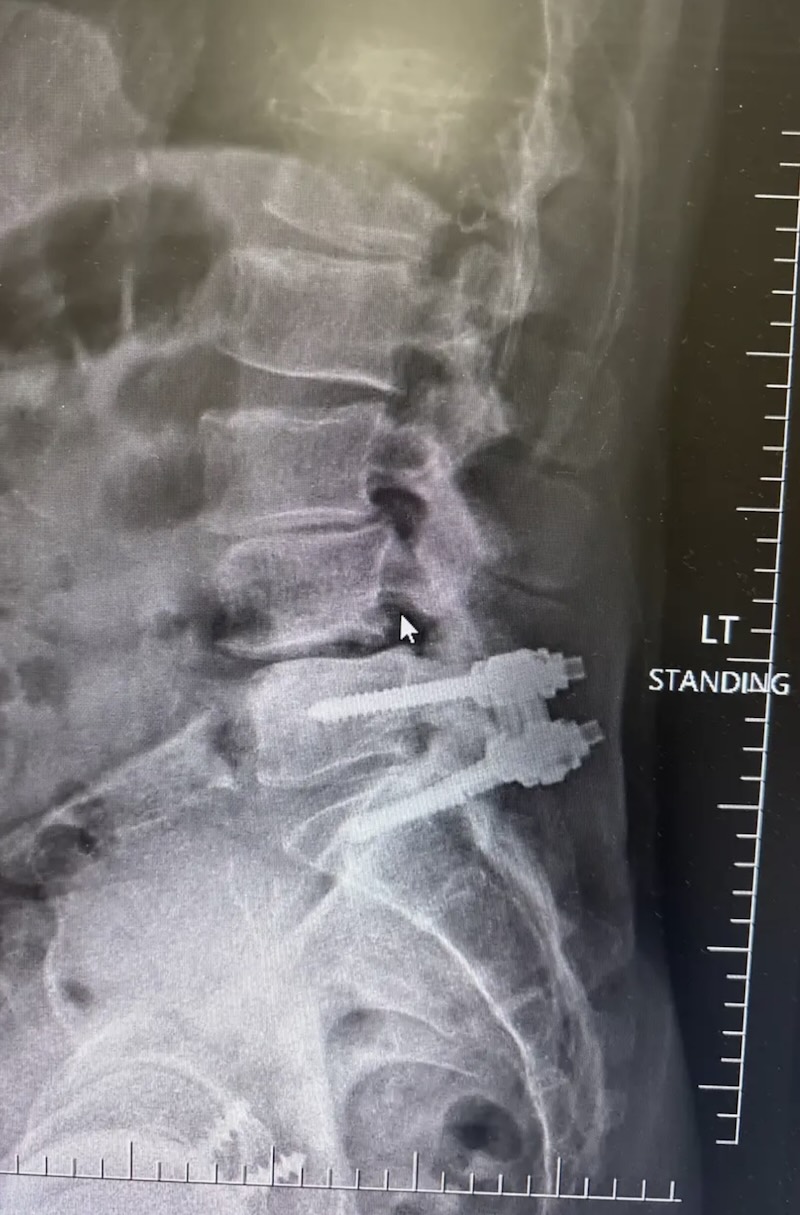

DePuy Monarch Offset Pedicle Screw System (Historical)

Screw Type: Pedicle Screws (Thoraco-lumbar)

By Location/Approach: Posterior Thoracic , Posterior Lumbar

By Procedure Type: Thoraco-lumbar-Pelvic Fixation

The MONARCH Spine System was originally produced by DePuy and is a titanium thoracolumbar pedicle screw fixation system. It is characterized by the pedicle screw with a polyaxial offset plate.